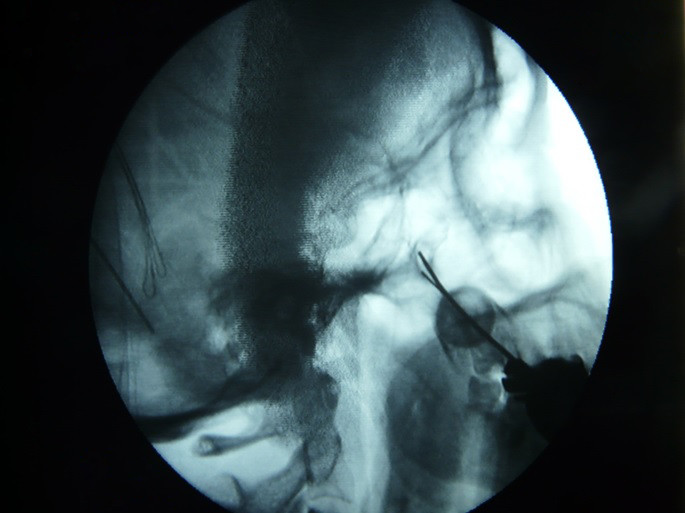

Fig.1. Es importante localizar la imagen del vaso invertido para dirigir hacia su vértice la aguja.

Fig.2. Es importante localizar la imagen del vaso invertido para dirigir hacia su vértice la aguja.